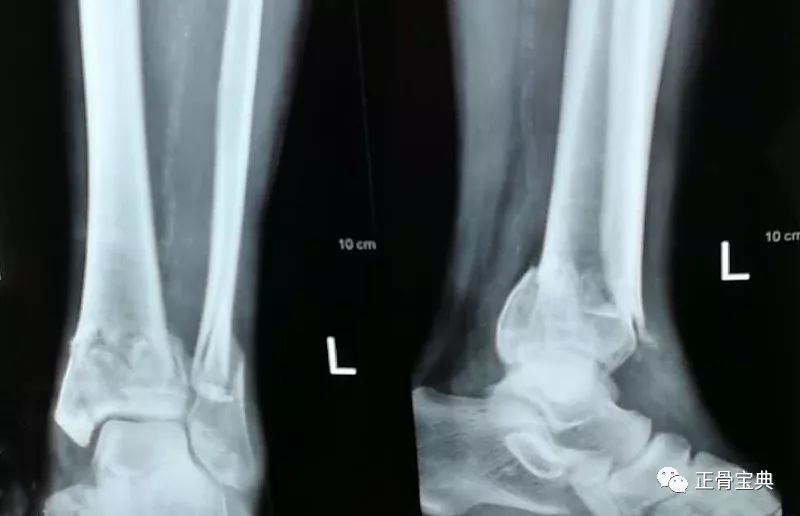

诊断:左胫骨下段粉碎性骨折,左腓骨上段骨折; 治疗:切开复位内固定 随访 讨论 术后好转出院。 发布于 2117 医联推荐你看 左胫腓骨骨折 左胫腓骨骨折 左胫腓骨骨折 共 11 个评论 发送左胫骨腓骨远端骨折及pillon骨折康复记录(有手术刀口图片,比较血腥,做好心理准备) carter 21年3月10日下午出的车祸,现在在医院躺了第二十一天。 住院后打了一个礼拜石膏给腿部消肿(不然开刀后伤口无法愈合),3月17日做的手术,做了五个小时。 (我刚被撞倒躺在地上拍的照) (躺在胫腓骨骨折在长管状骨 骨折中最常见。 胫腓骨干骨折 胫骨浅居皮下,缺乏肌肉附盖,故骨折后极易被骨折断端穿破皮肤。 多见儿童和青壮年。多为直接暴力所致。若发生在中下段,易引起延迟愈合或不愈合。 重定不好会产生创伤性关节炎。

正骨宝典 035 胫腓骨远端骨折 刘清春微创骨针01 正骨宝典 微信公众号文章阅读 Wemp